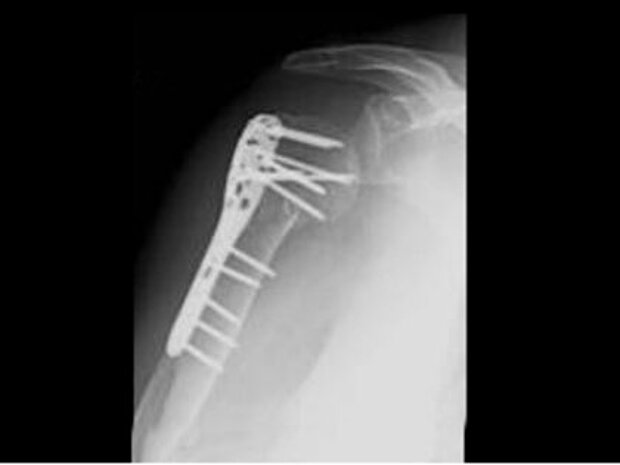

Behandlung von Knochenbrüchen

Im Jahr führt die Klinik für Unfallchirurgie und Orthopädie ca. 1800 Operationen am Knochen durch, davon etwa 900 endoprothetische Operationen.

Die Diagnostik umfasst neben der Erhebung des Unfallgeschehens, der ärztlichen Untersuchung in der Notfallambulanz insbesondere die Röntgendiagnostik konventionell. Wenn nötig, erfolgen computertomographische Spezialuntersuchungen.

Die Knochenbruchbehandlung erfolgt unter Verwendung modernster winkelstabiler Implantate nach Standard der Arbeitsgemeinschaft für Osteosynthese. Die operativen Eingriffe werden soweit möglich maximal gewebeschonend und minimalinvasiv durchgeführt.

Bei der operativen Therapie kommen u.a. zum Einsatz:

- Moderne Titan-Nägel - bei Frakturen von Röhrenknochen

- Titanplatten - bei gelenknahen Frakturen

- Titanstäbe - Intramedullärstifte (ESIN) bei kindlichen Knochenbrüchen

- Fixateur extern (äußere Festhalter) bei offenen Brüchen

- Fixateur intern (LISS-Systeme miminalinvasiv)